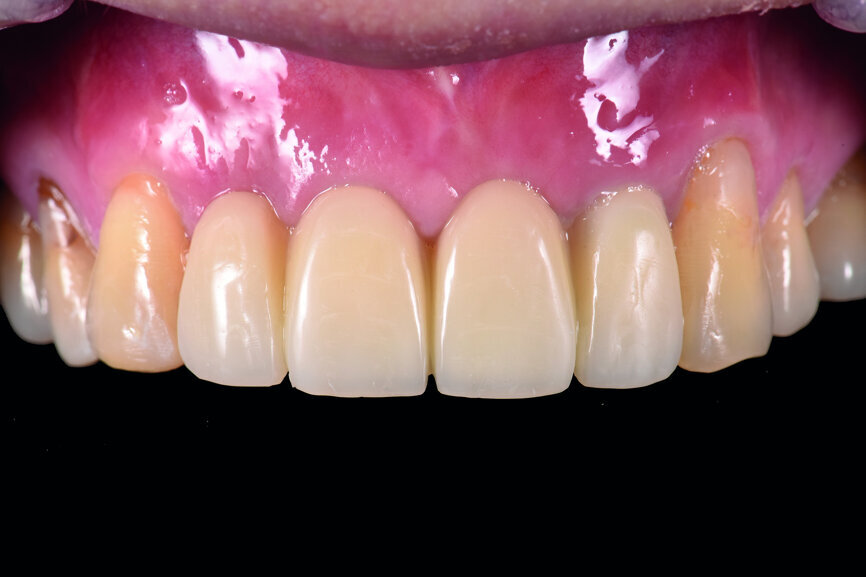

Fig. 43: Frontal view of the anterior teeth just after delivery.

The cast model was scanned step by step to obtain a digital model and this was integrated with a virtual articulator. The anterior guidance of the virtual articulator was set according to the data from the provisional restoration. Next, the design was completed on computer and the titanium-based zirconia abutment and fixed zirconia bridge produced via CAM. After staining and glazing, the final restoration was completed (Figs. 34–41). The final restoration demonstrated a good outcome, both aesthetically and functionally (Figs. 42–50).

This was a difficult implant-supported aesthetic restoration case. With the great efforts of the surgeons, prosthodontists and technicians, a satisfactory result was achieved.